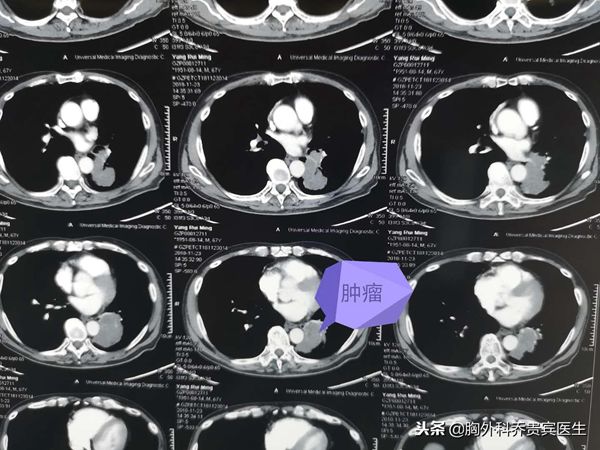

老人近期因为咳嗽,痰中带血去医院检查,结果发现左下肺有一个巨大肿块,肿块已经侵犯气管和血管。经过病理活检,确诊是一个大细胞肺癌。

近日,用了三个小时给老人完成了这个艰难的手术,胸腔镜下左下肺切除,支气管成形,因为化疗后粘连,术中渗血比较多,又要做腔镜下的吻合。术中也差点因为情况严重而中止手术,最后还是在坚持和努力下完成了。术后老人再配合相应的化疗,希望能达到预期的效果。